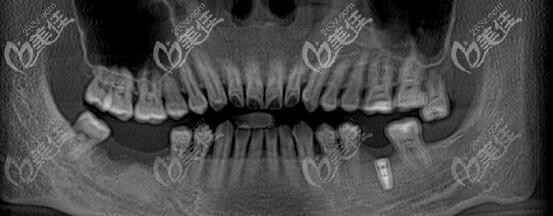

牙齒情況:左下后牙種植過一顆,右下后牙缺失兩顆;

術(shù)前照片:

術(shù)后照片: